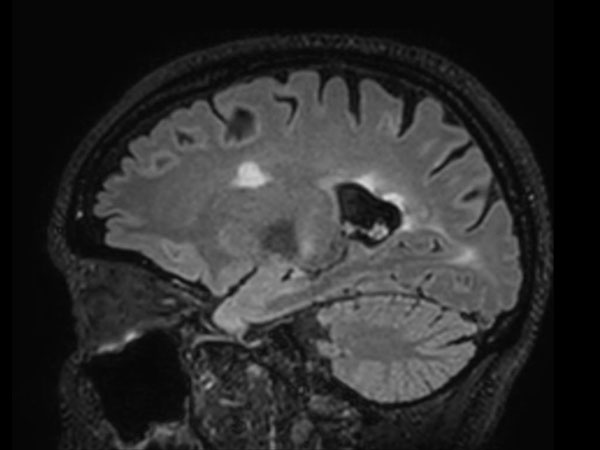

T2w TSE MultiVane XD